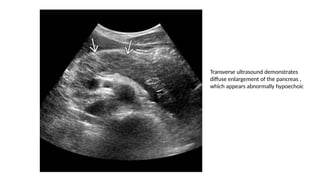

Transverse ultrasound demonstrates

diffuse enlargement of the pancreas ,

which appears abnormally hypoechoic

Transverse ultrasound demonstrates diffuseenlargement of the pancreas , which appears abnormally hypoechoic